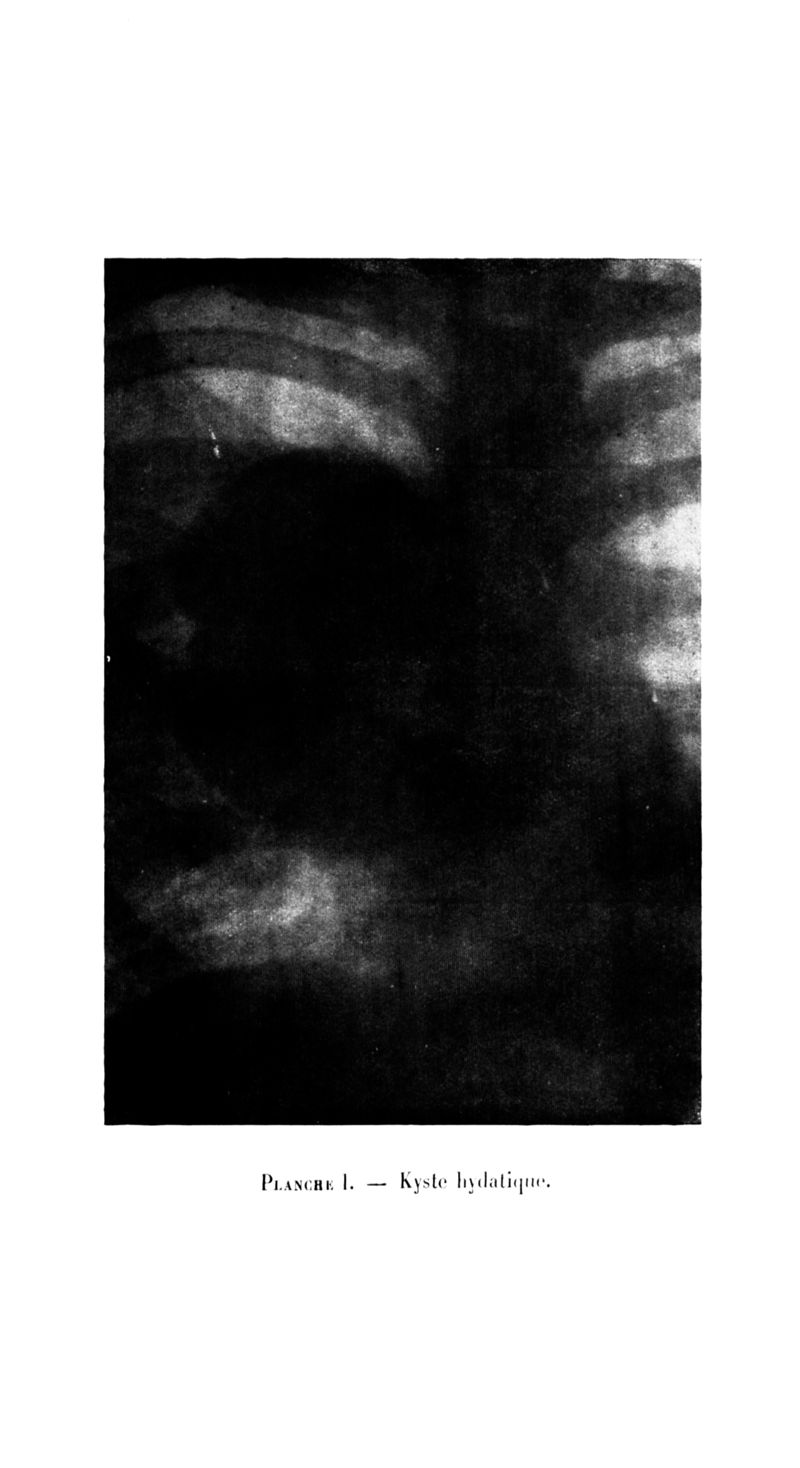

Archives de médecine et pharmacie navales

1924, n° 114. - Paris : Imprimerie nationale, 1924.